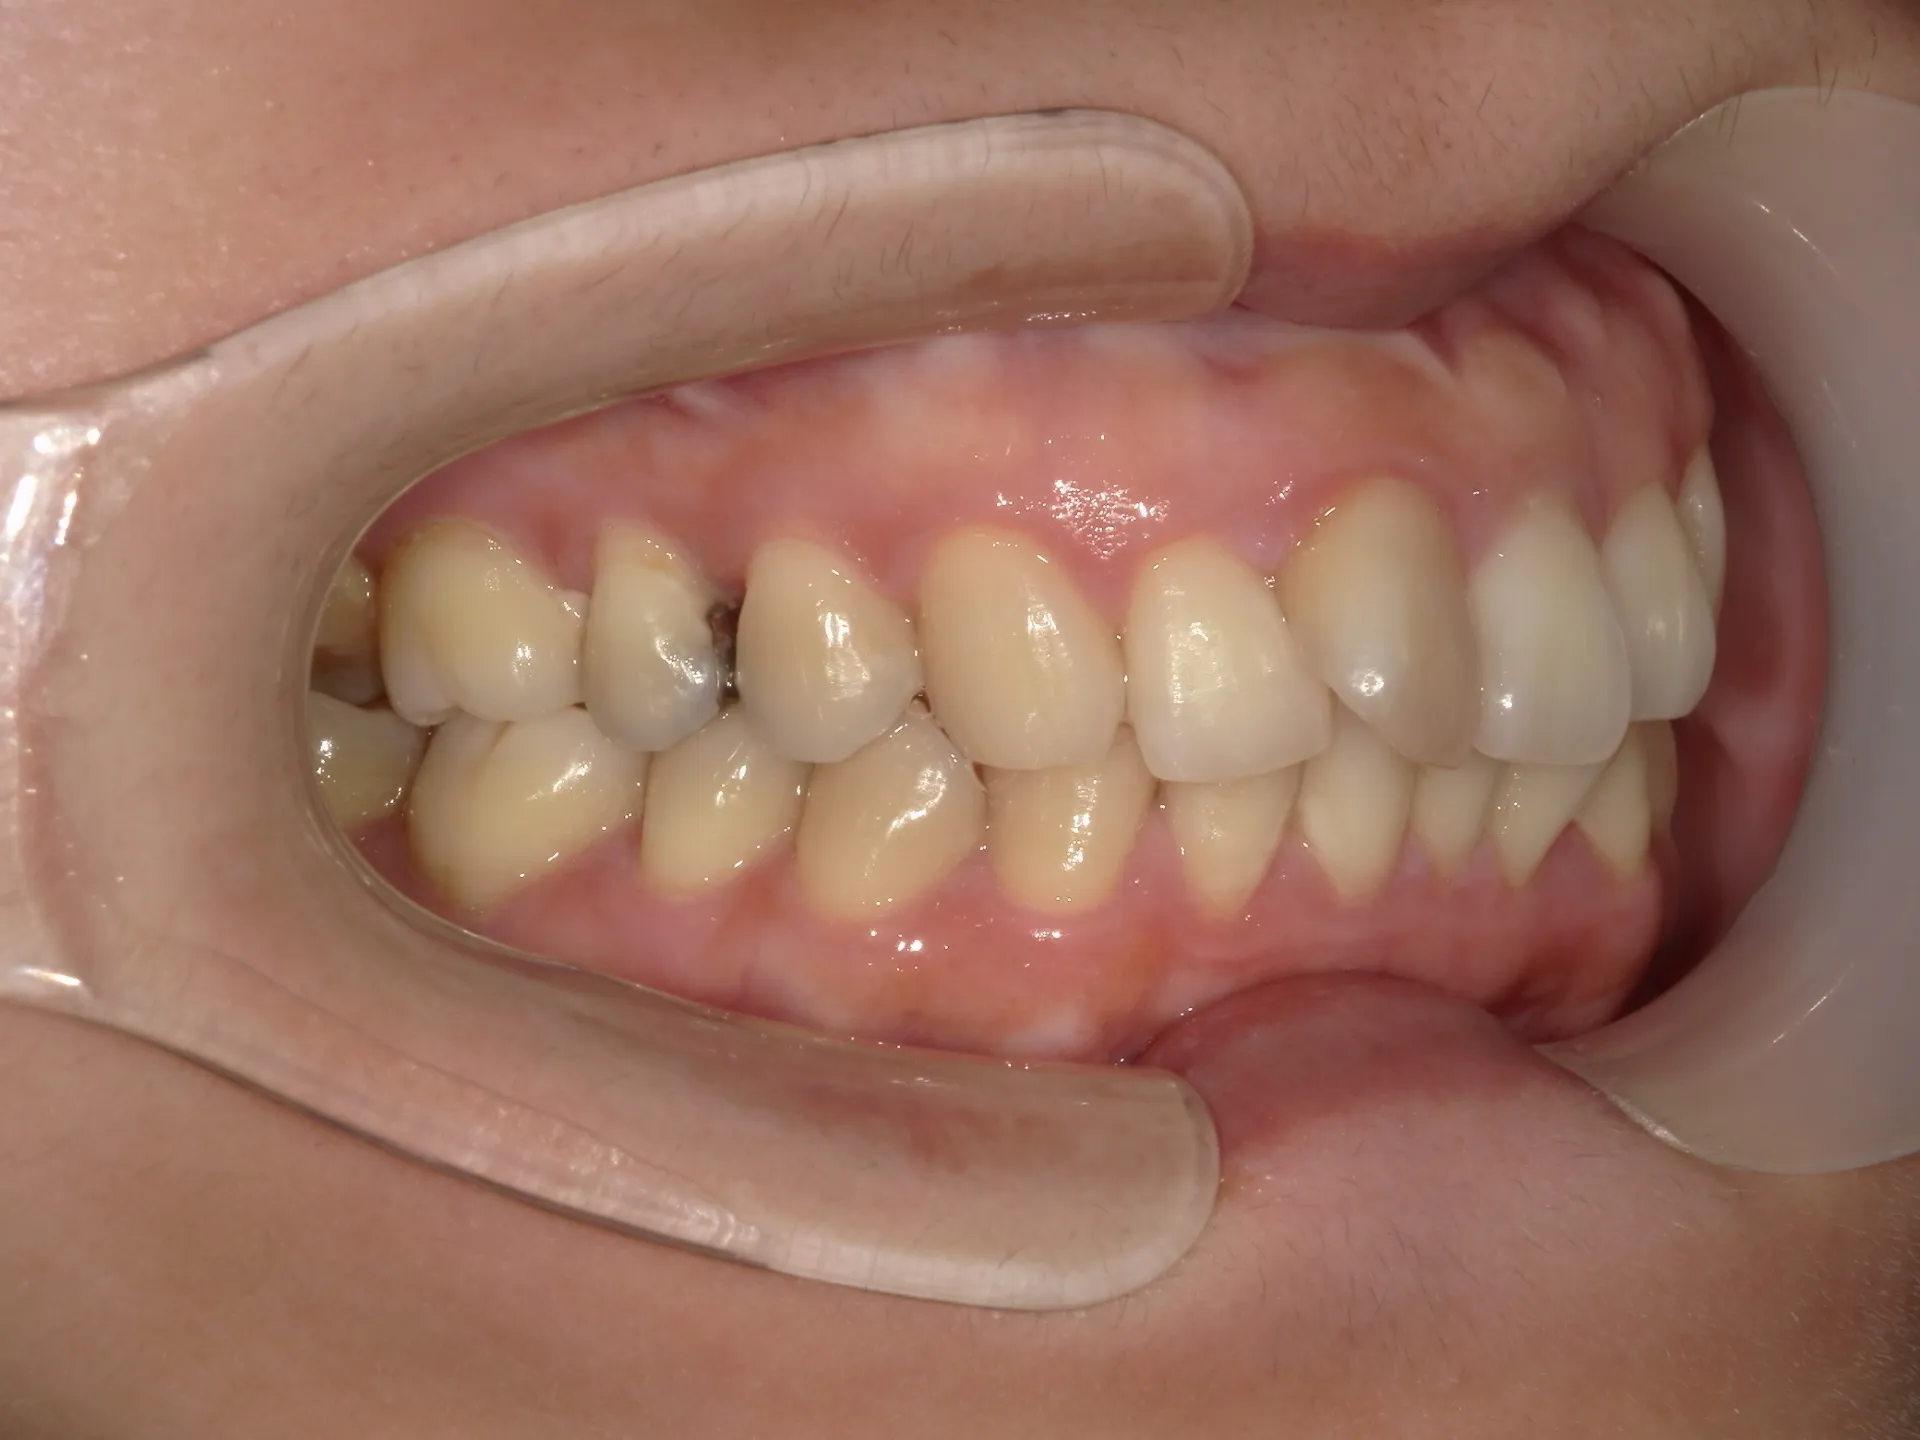

上の前歯が1本大きくねじれ、更にその歯に変色も見られました。

下の歯もスペースがなくガタついている状態の歯並びでした。

歯のねじれと歯の色を同時に治す方法として、セラミックの被せものがあります。

セラミックの被せを入れて歯の形や色、位置も治すことができますが、今回の状態で1本分のセラミックの被せを入れるとかなり細くなる被せを入れなければなりません。なぜかと言うと歯がねじれている原因は歯が真っ直ぐ生えるスペースがなかったことです。ここに無理やり被せで治そうとすると通常の歯の約半分程度の幅の被せになってしまいます。

そのため今回は通常の矯正治療とその後にご自身の歯を利用してウォーキングブリーチを行いました。